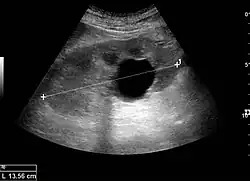

Cortical thickness should be estimated from the base of the pyramid and is generally 7–10 mm. If the pyramids are difficult to differentiate, the parenchymal thickness can be measured instead and should be 15–20 mm (Figure 3). The echogenicity of the cortex decreases with age and is less echogenic than or equal to the liver and spleen at the same depth in individuals older than six months. In neonates and children up to six months of age, the cortex is more echogenic than the liver and spleen when compared at the same depth.[1]

Figure 3. Measures of the kidney. L = length. P = parenchymal thickness. C = cortical thickness.[1]